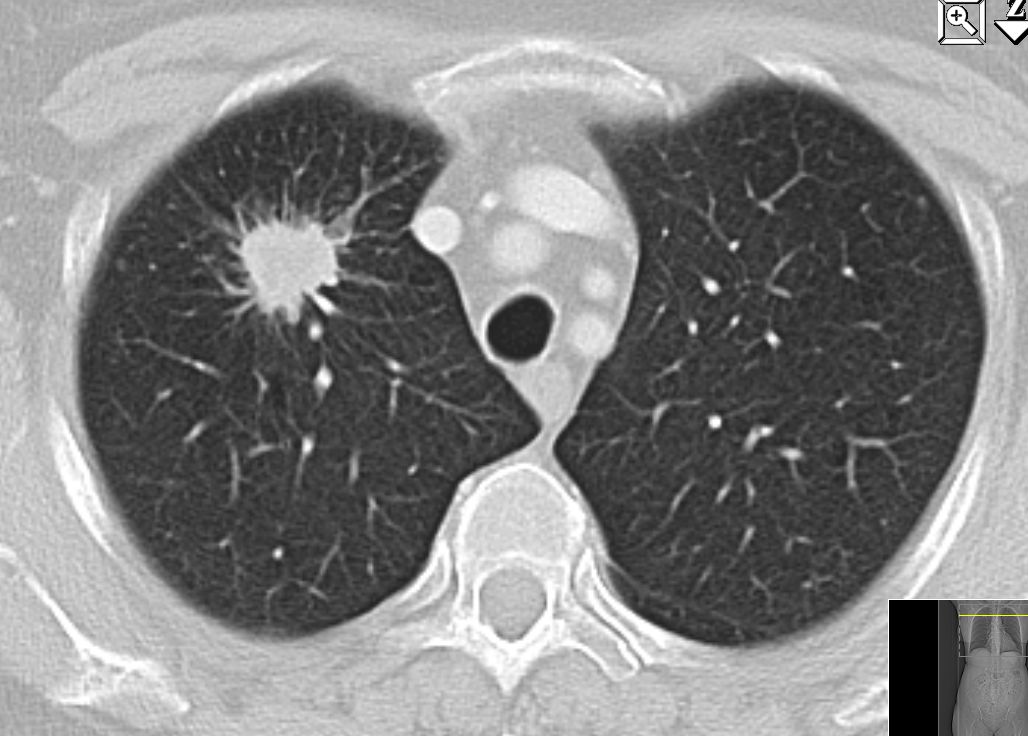

50-jähriger Mann mit einem Adenokarzinom im rechten Oberlappen![]() |